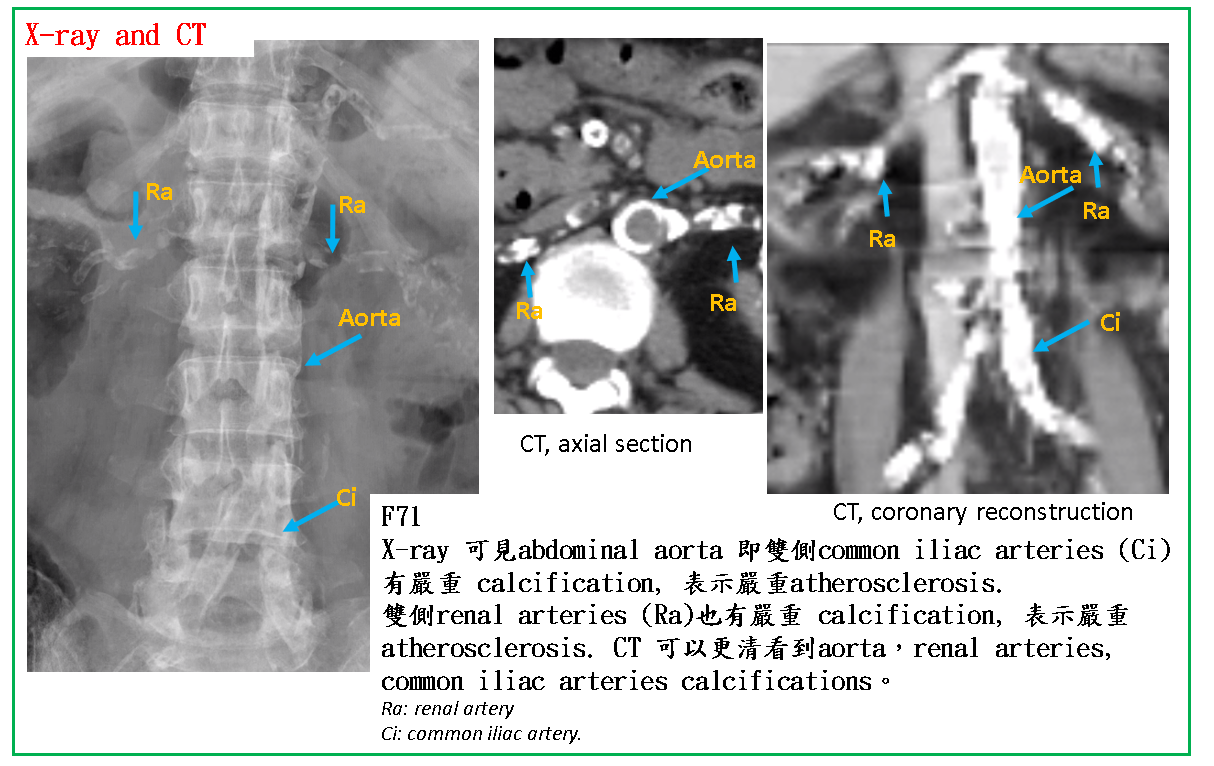

X光影像: X-ray是依據鈣化診斷atherosclerosis, 因此X-ray看到時,都是比較嚴重的atherosclerosis.

Thoracic aorta, abdominal aorta, 因為管徑大,atherosclerosis 引起的鈣化在chest X ray 及KUB可以看到。其他像renal artery, femeral artery等中型血管也可以由X ray看出。

CT: CT影像比X-ray 能更清楚顯示動脈壁鈣化及管腔狹窄情況.